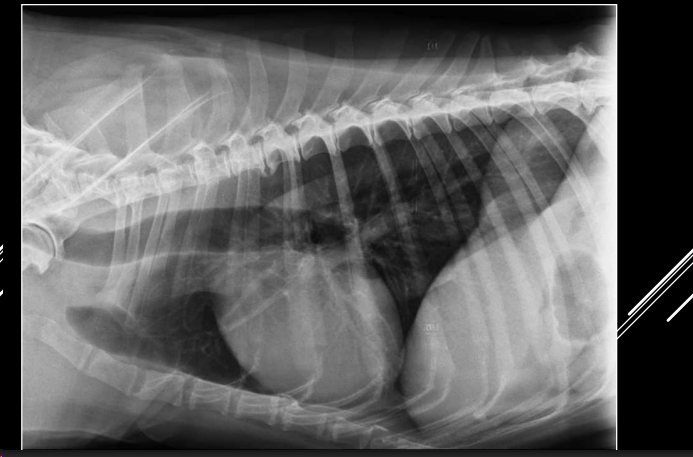

Neumotórax

Si hay un neumotorax y neuromediastino, el neumomediastino siempre es el causante

- Aire en cavidad pleural.

- RX:

- Desplazamiento dorsal del corazón (LL).

- Colapso pulmonar.

- Trama pulmonar no llega a pared torácica.

- Espacio radiolúcido entre pulmón y pared.

Cuando hay un neumotorax, al retraerse el pulmon se presentara un patron alveolar. Si el aire puede ir a ambos lados las presiones se compensan, anotensión. Si solo entra y no sale aumentara la presion y tendremos un neumotorax atensión